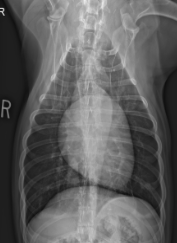

ID View

Left Lateral